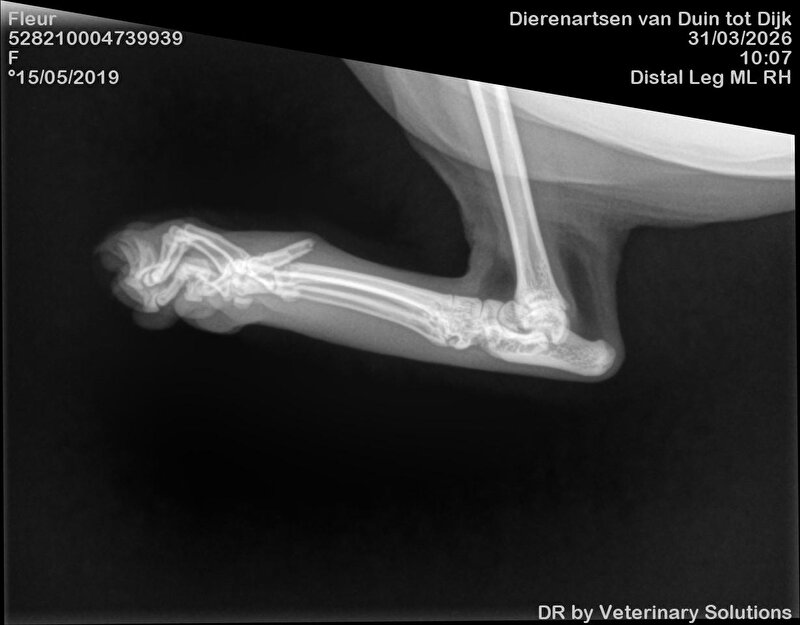

Dag 2: ik laat Fleur achter voor het maken van de foto's. Aan de assistente vertel ik dat Fleur zich goed gedraagt. Fleur is nml best een lief poesje. Er worden 3 foto's gemaakt en deze hoop ik nog te ontvangen om hier te kunnen plaatsen. 2 teentjes gebroken en 1 bot dusdanig naar buiten gekanteld dat deze bijna door steekt.